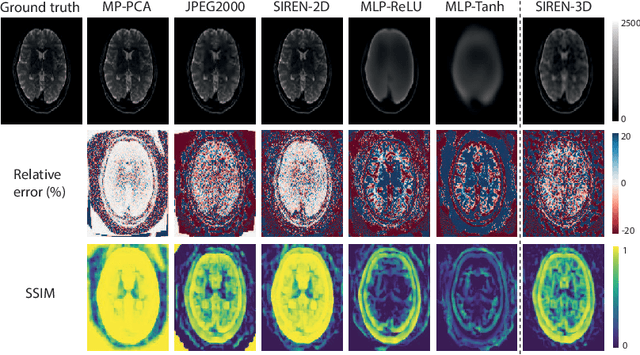

Abstract:In this work, we evaluate how neural networks with periodic activation functions can be leveraged to reliably compress large multidimensional medical image datasets, with proof-of-concept application to 4D diffusion-weighted MRI (dMRI). In the medical imaging landscape, multidimensional MRI is a key area of research for developing biomarkers that are both sensitive and specific to the underlying tissue microstructure. However, the high-dimensional nature of these data poses a challenge in terms of both storage and sharing capabilities and associated costs, requiring appropriate algorithms able to represent the information in a low-dimensional space. Recent theoretical developments in deep learning have shown how periodic activation functions are a powerful tool for implicit neural representation of images and can be used for compression of 2D images. Here we extend this approach to 4D images and show how any given 4D dMRI dataset can be accurately represented through the parameters of a sinusoidal activation network, achieving a data compression rate about 10 times higher than the standard DEFLATE algorithm. Our results show that the proposed approach outperforms benchmark ReLU and Tanh activation perceptron architectures in terms of mean squared error, peak signal-to-noise ratio and structural similarity index. Subsequent analyses using the tensor and spherical harmonics representations demonstrate that the proposed lossy compression reproduces accurately the characteristics of the original data, leading to relative errors about 5 to 10 times lower than the benchmark JPEG2000 lossy compression and similar to standard pre-processing steps such as MP-PCA denosing, suggesting a loss of information within the currently accepted levels for clinical application.